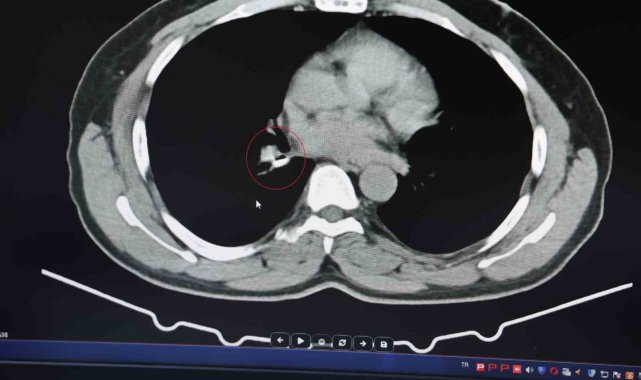

Şenyiğit, o maddenin zamanla akciğer yapısının özelliğini aldığını ve orada yabancı bir madde olarak kaldığına değinerek, "Hastamıza maalesef 2 yıldan beri astım tanısı konulmuş ve sürekli tedavi verilmiştir. Hasta bize geldiği zaman yapılan tomografide sağ akciğer ana bronşun distalinde şüpheli lezyon gördük. Uyguladığımız bronskokopide yabancı maddenin silikon olduğunu tespit ettik. Onu çıkardıktan sonra da hastada bir rahatlama meydana geldi" dedi.